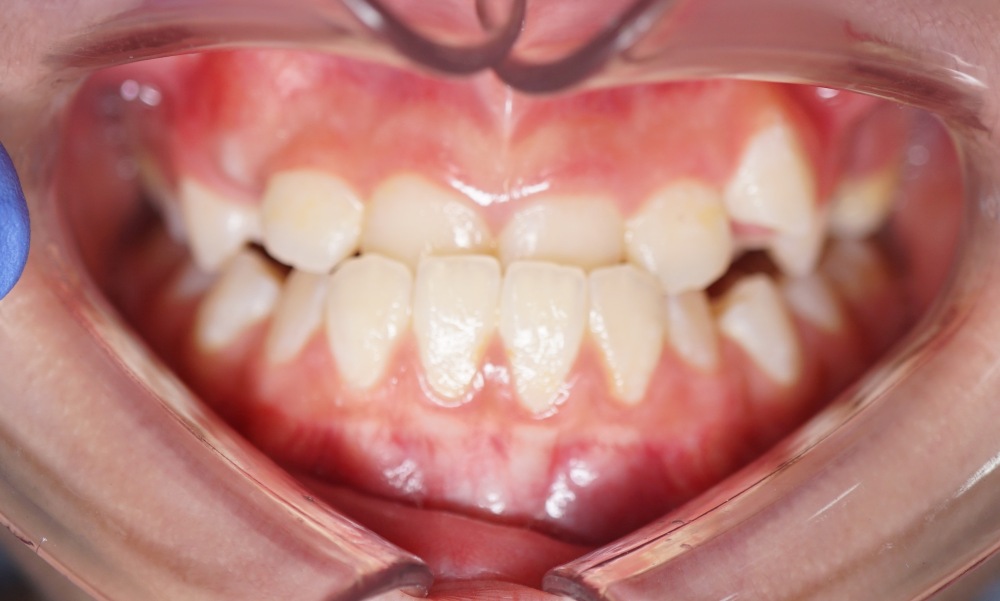

Case Study 2

Upper jaw growth → Corrected reverse bite

Age

9 years old

Parent Concern

“Her lower jaw covering upper jaw, how can Dr help with this?”

Clinical observation

Upper jaw is under-developed.

Treatment Approach

Promote mid face growth (Clear Aligner + facemask)

Treatment Outcomes

Her reverse bite was corrected in just a few months! 😁

Before (March 25)

After (Sep 25)

Actual patient results. Individual outcomes may vary.